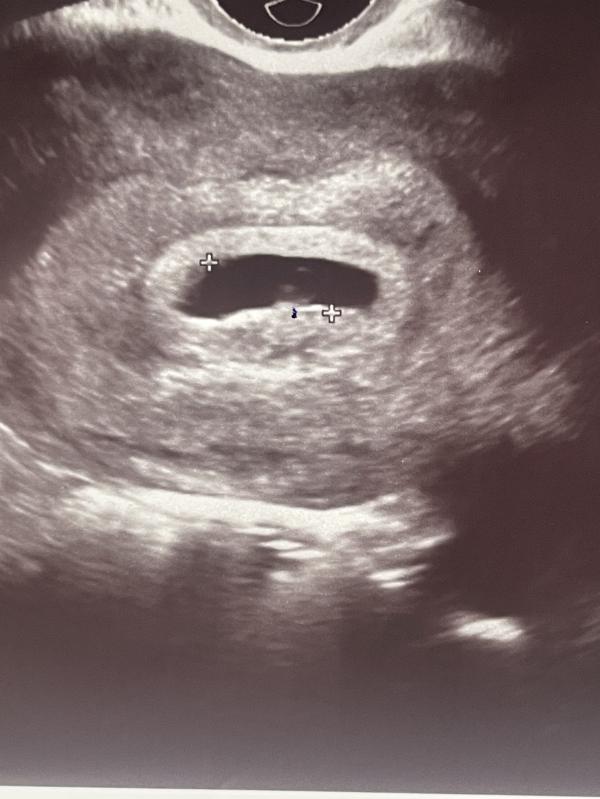

ПЯ выросло,оно 16 мм,есть ЖМ 2,5.

Врач сказал,что эмбрион только-только начал появляться,буквально 1 мм.